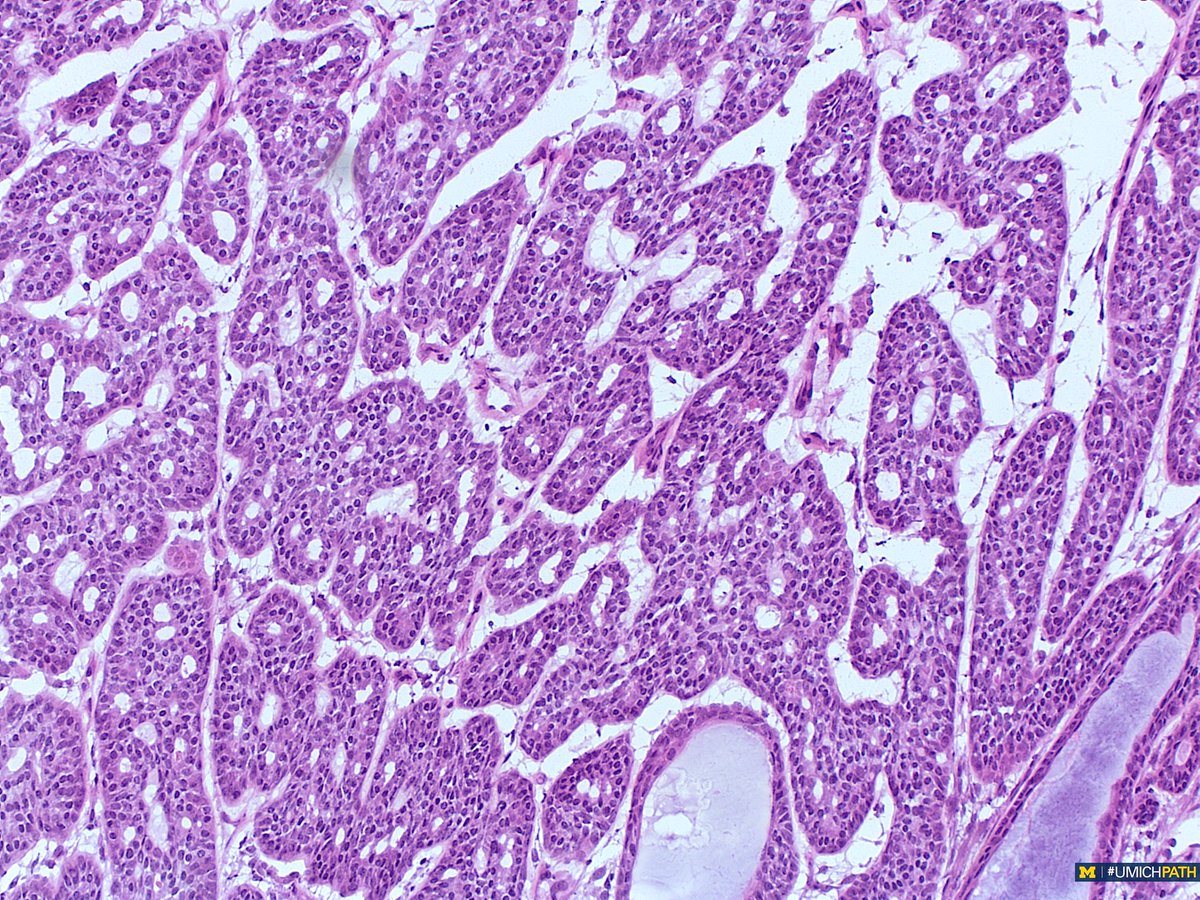

@UMichPath

🔬: #COTW from @MeredithKHerman! Intraoperative Frozen Consult of a parotid mass from a 60yo F. What is your differential diagnosis? #UMichPath #Pathology